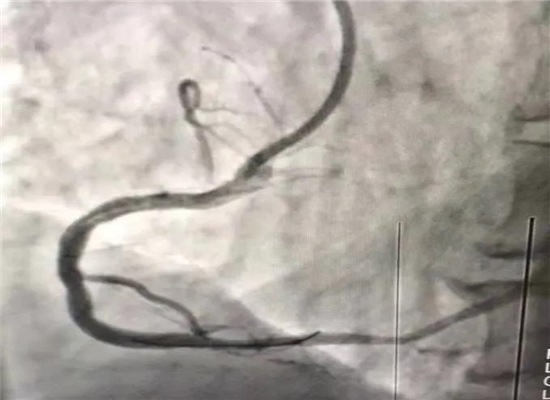

早上8时48分,120急救中心接到六麻卫生院的出诊电话,有一名胸痛病人7时左右在家晕倒,家属急送到六麻卫生院,初诊为急性心肌梗塞,病情危重,需马上转院到我院进一步治疗。急诊医学科立即启动急性心肌梗塞救治绿色通道预案,立即出车,于9时40分到达六麻卫生院,到诊后复查心电图并立即上传微信群会诊,确诊后为患者按急性心肌梗死急诊介入治疗做准备,监护返回。提前通知心血管内科医师到急诊医学科等侯会诊,并同时激活导管室。10时45分患者顺利转运回我院,心内科医师会诊后快速完成知情谈话及签字,10时57到达导管室,由杨勇、张轩两位主任进行介入手术,术中发现患者右冠状动脉100%闭塞,11时46分顺利植入一枚支架,患者的心肌得以重新灌注,11时58分手术结束,术后患者胸痛症状明显缓解,12时12分转到CCU监护。

介入手术后